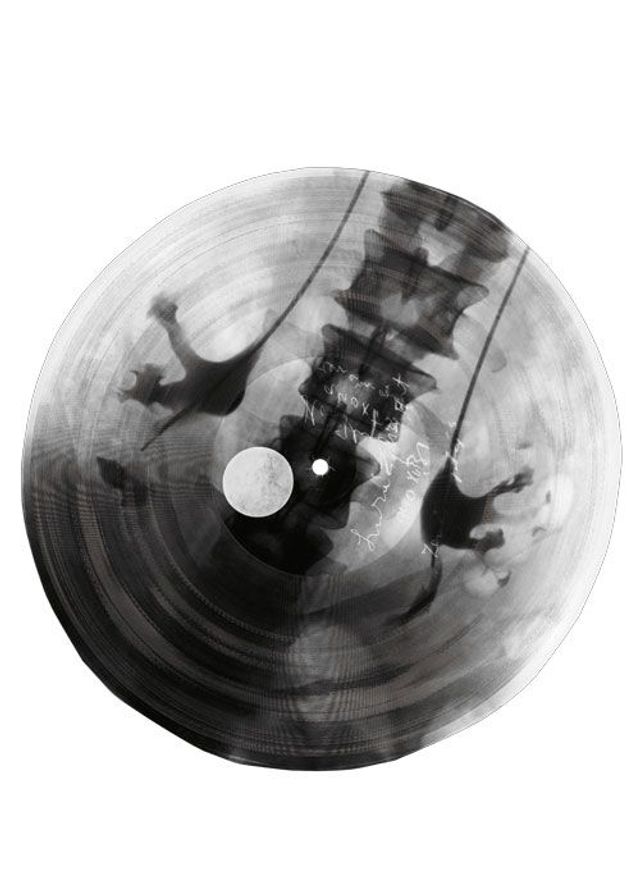

»Was haben wir für einen schönen Abend«, singt Anna Kapitány, während sich die Röntgenaufnahme eines menschlichen Schädels auf dem Grammophon dreht. Musik auf Skeletten – das wäre eine wunderbare Marketing-Idee für eine Black-Metal-Band. Aber zu Kapitánys heiterem Bigband-Swing tanzten die Ungarn in den Dreißiger- und Vierzigerjahren. Diese Lieder wurden live gespielt und im Radio übertragen. Nur für die Ewigkeit ließ sich ihre Musik schwer festhalten: Im Krieg war Schellack selten, das Harz aus den Ausscheidungen der Lackschildlaus musste aus Indien importiert werden. Also suchten Musikliebhaber und Mitarbeiter des ungarischen Radios eine Alternative – und fanden sie in Krankenhäusern.

Die Zelluloidfolien, auf denen gebrochene Rippen, ausgerenkte Gelenke, tuberkulöse Lungen abgebildet wurden, waren gerade dick und haltbar genug, dass man mit einer Plattenschneidemaschine Tanzmusik oder Ansprachen von Politikern hineingravieren konnte. Die biegsamen Platten wurden mal mehr, mal weniger sorgfältig in eine runde Form geschnitten, sodass sie auf den Teller des Grammophons passten. Für die Nadel war es egal, ob sie von Rillen im Schellack oder im Zelluloid zum Schwingen gebracht wurde. Zu lange durfte das Stück nicht dauern – auf eine Scheibe mit 23 bis 25 Zentimetern Durchmesser passten nicht viel mehr als drei Minuten. Ein halbes Jahrhundert zuvor waren die Röntgenstrahlen entdeckt und das Grammophon erfunden worden, nun verschmolzen sie zu einer Technik.

Nach dem Fall des Eisernen Vorhangs hat der ungarische Fotograf József Hajdú die Schönheit dieser Scheiben neu entdeckt und besonders gelungene Exemplare aus unterschiedlichen Sammlungen fotografiert. Bei vielen ist heute nicht mehr nachvollziehbar, welche Musik oder welcher Sprecher da zu hören ist. Hajdú ist davon begeistert, dass die Scheiben in zweifacher Hinsicht Themen unserer Zeit vorwegnahmen: »Zum einen sind sie Recycling, zum anderen eine frühe Form von Multimedia.« Die anonymen Raubkopierer, sagt Hajdú, hätten sich sichtlich Mühe gegeben, besonders eindrucksvolle Röntgenaufnahmen für ihre Aufnahmen zu wählen.

Nach dem Krieg erlebten die Röntgenscheiben eine zweite Blüte in der Sowjetunion: Rock ’n’ Roll, die Beatles, amerikanischer Jazz, Gaunerlieder mit antisowjetischen Texten – alles, was die staatliche Plattenfirma »Melodija« nicht im Programm hatte, wurde in Untergrundstudios als Bootleg-Pressung vervielfältigt und konspirativ als »Jazz auf Knochen« oder »Musik auf Rippen« verbreitet – eine frühe Form von Musikpiraterie, mit echten Schädeln und Knochen. Schwarzhändler verkauften die labbrigen Scheiben vor den Eingängen zu den staatlichen Musikgeschäften. Wer die Technik erfunden hat, ist heute nicht mehr nachvollziehbar. Gut möglich, dass Menschen an mehreren Orten, ohne voneinander zu wissen, mehr oder weniger gleichzeitig auf die Idee kamen, Musik in Röntgenplatten zu ritzen. Sicher ist, dass das Verfahren bald in der ganzen Sowjetunion verbreitet war. Manche Produzenten wurden für Jahre ins Lager geschickt – und gingen am Tag nach ihrer Entlassung wieder ins Tonstudio.

Fotos: József Hajdú